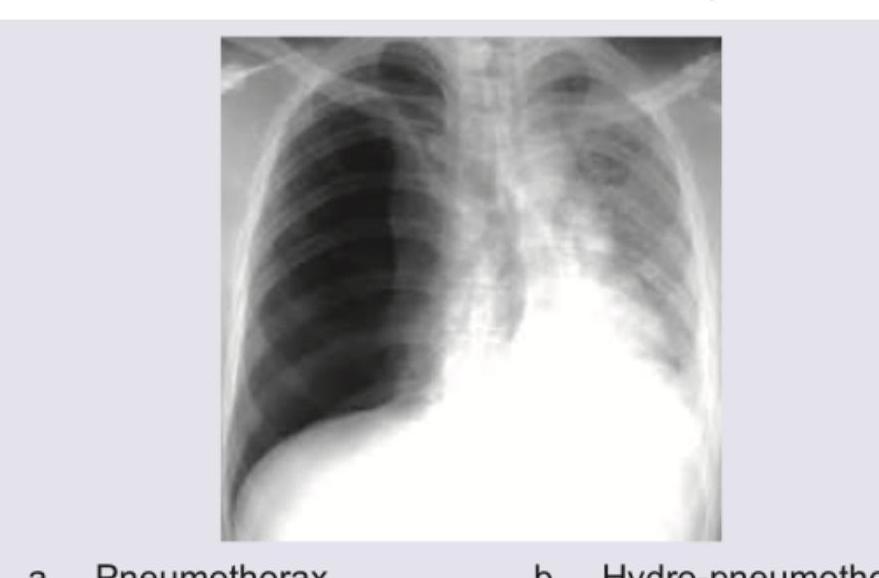

A patient presented with sudden onset difficulty in breathing with RR 28/min, normal blood pressure. X-ray was taken which is given below. What is the diagnosis?

Question 4: A patient presented with sudden onset difficulty in breathing with RR 28/min, normal blood pressure. X-ray was taken which is given below. What is the diagnosis?

- A. Pneumothorax

- B. Hydro-pneumothorax (Correct Answer)

- C. Pleural effusion

- D. Consolidation

Explanation: ***Hydro-pneumothorax*** - The chest X-ray clearly shows a **horizontal air-fluid level** in the right hemithorax, indicating the presence of both air (pneumothorax) and fluid (hydrothorax) within the pleural space. - The patient's sudden onset **difficulty in breathing** and **tachypnea (RR 28/min)** are consistent with significant lung pathology like a hydropneumothorax, which compromises lung function. *Pneumothorax* - A simple pneumothorax would show only **air in the pleural space**, characterized by a visible visceral pleural line and absence of lung markings beyond it. - While there is air present, the prominent **fluid level** rules out a diagnosis of pneumothorax alone. *Pleural effusion* - Pleural effusion presents as a **blunting of the costophrenic angles** and a meniscus sign, where fluid conforms to the shape of the thorax. - This image shows a **straight air-fluid level**, not a typical meniscus, indicating the presence of air in addition to fluid. *Consolidation* - Consolidation refers to the **filling of alveolar spaces with fluid or exudate**, appearing as an opacification within the lung parenchyma. - Consolidations typically do not present with a **horizontal fluid level** in the pleural space; they are intraparenchymal.